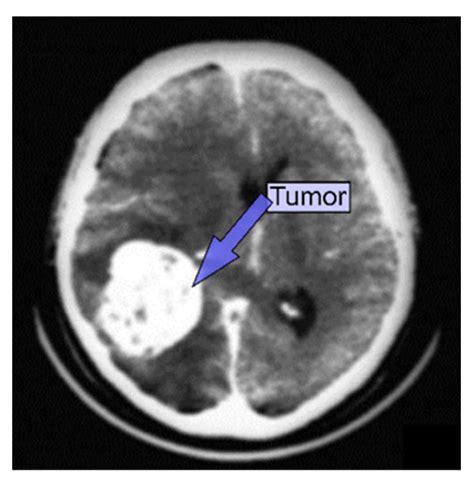

Doctors often order this scan if they suspect an abnormality such as a tumor, cyst, or inflammation. By visualizing the physical landscape of the brain, medical experts can identify the location, size, and shape of potential growths, which is crucial for determining the next steps in a clinical treatment plan.

Once the scan is complete, a radiologist—a doctor specialized in interpreting medical images—will analyze the data. They look for masses, swelling, or structural anomalies that could indicate cancer or other conditions. The results are typically sent to your primary physician or neurologist, who will then discuss the findings with you during a follow-up appointment.

It is important to remember that a "positive" finding on a scan does not automatically confirm cancer. Many non-cancerous conditions, such as benign cysts or infections, can mimic the appearance of a tumor. Further diagnostic procedures, such as a biopsy or an MRI with gadolinium contrast, may be required to reach a definitive diagnosis.